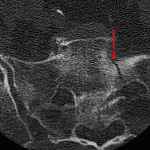

- Nondisplaced bilateral sacral fractures with fracture extension into the left S1 foramen

- Sacral insufficiency fractures

Bilateral sacral insufficiency fractures, with extension into the left S1 neural foramen.